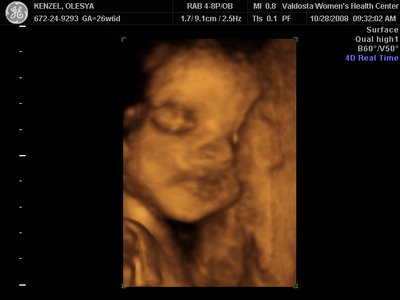

Ксюнь, а мы вообще не поняли. Она на всех фотках разная, да еще размытость такая. Пуповина то на носу болталась, то руками-ногами закрывалась. Главное что четкости нет совсем. Лоб у мужа тоже большой, а носы и губы зачастую на 3Д-4Д выходят разамазанно-пухло-приплюснутыми Поставлю для наглядности фотку моей средней-Джианки с 3Д УЗИ, там видно черты намного лучше и она на себя ту похожа сейчас, хотя родилась мне совсем на фото УЗИ не казалась похожей.

| Вложения: |

KENZEL,OLESYA_3.JPG [ 56.84 КБ | Просмотров: 1428 ]

Еще одна Джианнка:

KENZEL,OLESYA_5.JPG [ 60.02 КБ | Просмотров: 1513 ]